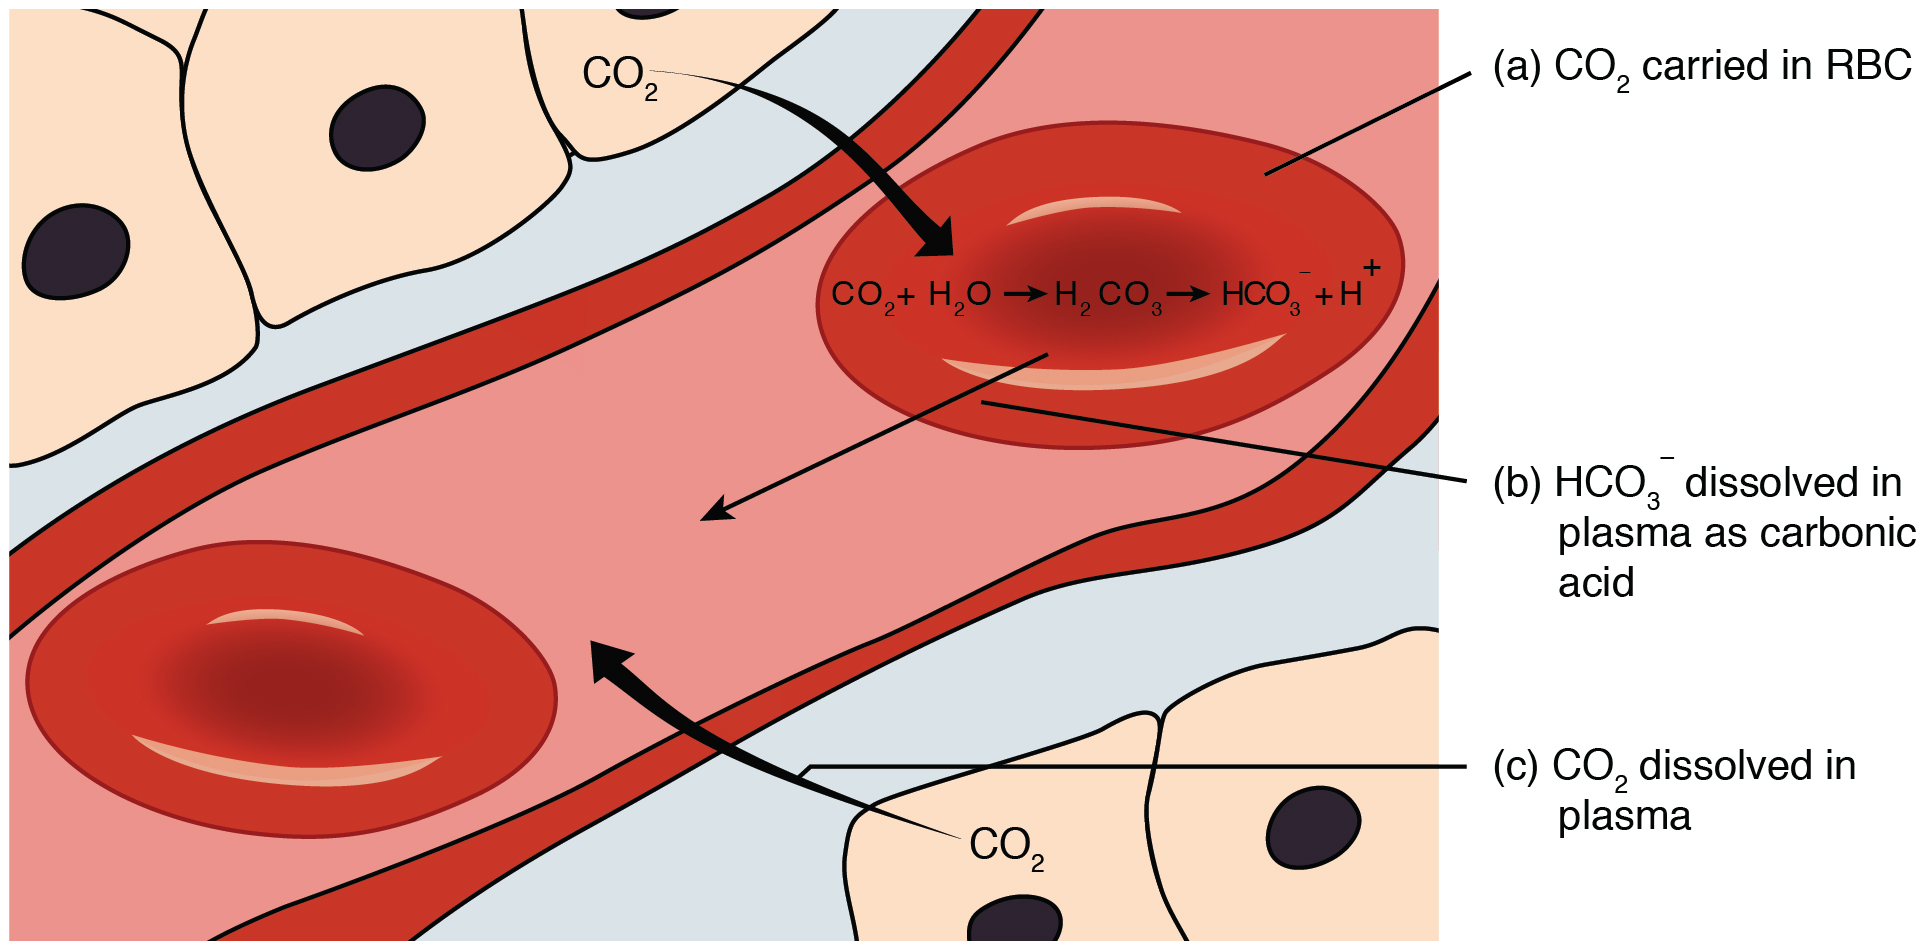

Hypercapnea – is also known as hypercarbia. It is a condition related to high carbon dioxide levels in the body. Carbon-dioxide can get built up in the blood if the body doesn’t successfully get rid of it within time. Conditions that either increase the levels of carbon-dioxide in the body or prevent the waste carbon-dioxide from getting to the lungs and discarded are usually the main causes of hypercapnea. Illnesses related to lung, brain, muscles and nerves are usually the most common causes. Hypercapnia is different to hypoxemia as hypercapnia is the condition with high carbon-dioxide levels in blood whereas hypoxemia is low oxygen levels in blood.